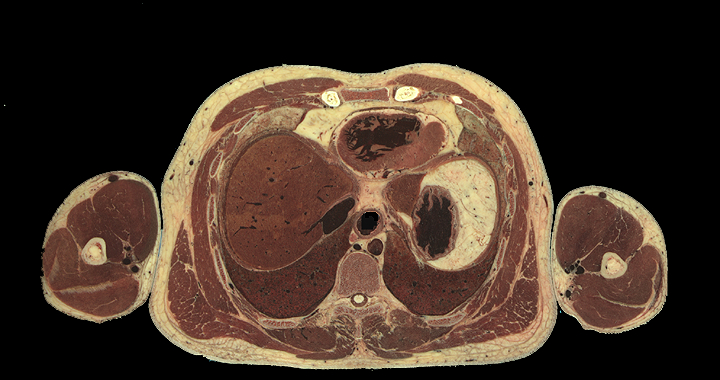

Thorax structures, high resolution